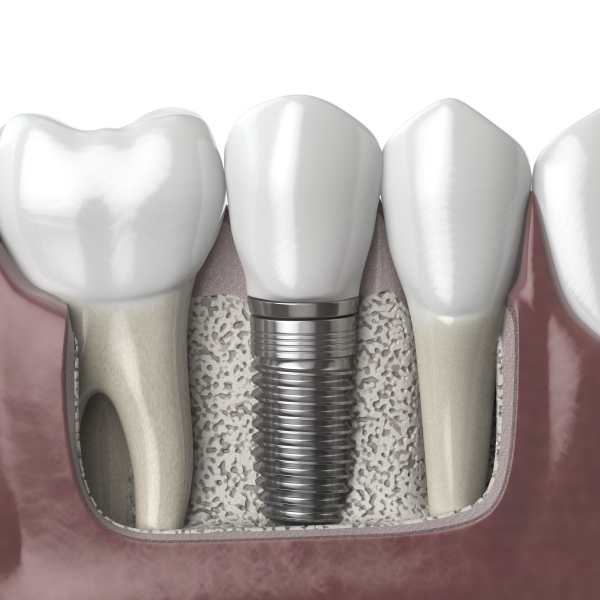

이미 나빠진 치아를 제거한 후 같은 자리에

이를 보완하여 역할을 대신하게 하는 방법은

기능적인 상황은 물론이며 외관적 문제를

해결하는 방식이라고 했어요.

이 기능을 대신할 수 있도록

알맞은 치과 진료를 진행하기 위해

적합한 계획을 수립해야 했어요.